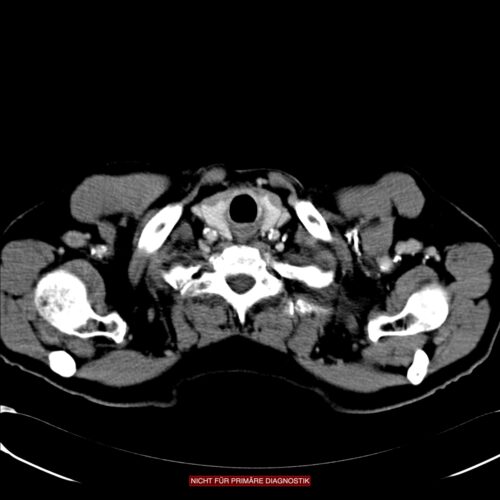

Endosonografie

Zum lokalen Staging und zur Abschätzung der Eindringtiefe in die Wand des Ösophagus dient die Endosonografie. Auch möglicherweise befallene Lymphknoten lassen sich darstellen.

Nach der TNM-Klassifikation werden T1a Tumoren durch Infiltriatin der Mukosa bis in die Lamina muscularis mucosae definiert. Die T1b Tumoren infiltrieren in die Submukosa, wobei drei unterschiedliche Eindringtiefen unterschieden werden. T2-Tumoren beziehen sich auf die Muscularis, T3 erreichen die Adventitia und T4-Tumoren infiltrieren Nachbarorgane.